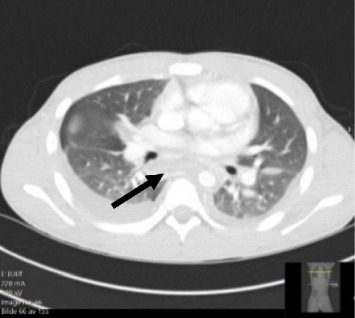

A male in early adolescence presented with 1 week of chest pain, respiratory symptoms and diarrhoea. Thoracic computed tomography (CT) revealed suspicious findings of necrotising mediastinitis without signs of a descending infection. The patient underwent bilateral thoracotomy and laparotomy with several revisions. After 58 days in the hospital, the patient was discharged home, fully recovered, with no sequelae. This case highlights the importance of a multidisciplinary approach when managing severe and rare conditions, emphasising the need for early diagnosis and prompt, appropriate surgical treatment.